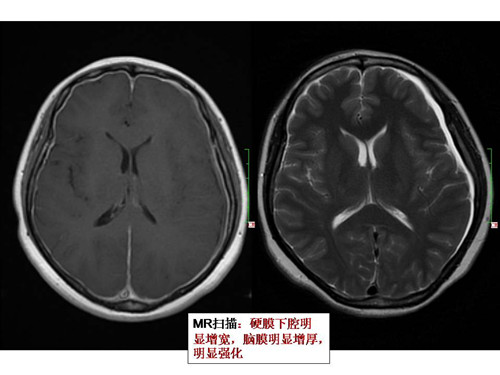

您知道反复头晕呕吐需做MRI检查吗?

您了解MRI吗?您知道当反复头晕呕吐时需要进行MRI检查吗? 42岁的张女生被反复头晕、时而呕吐等症状缠绕半年,并且在站立时病状会加重,躺下时才能减缓。 忧心忡忡的张女士在家人的陪同下曾到安博体育 进行过头颅CT等检…